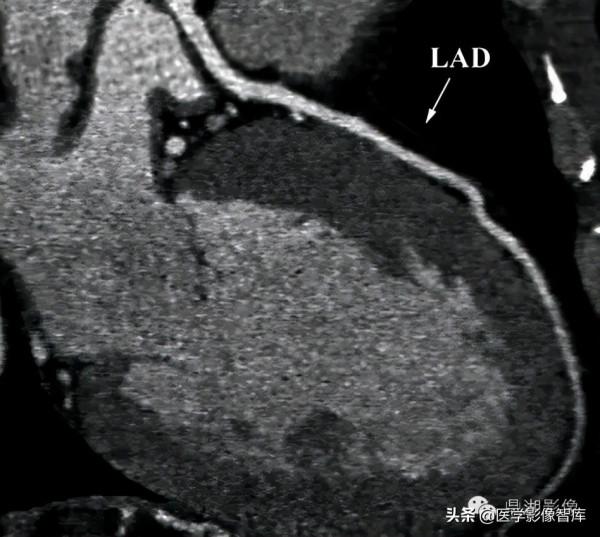

心臟

冠脈

冠脈解剖:

前降支 left anterior descending branch LAD

Maximum intensity projection (MIP)

心肌梗死好發部位為左心室前臂心尖部室間隔前2/3。

心肌梗死的好發部位依次為:

①左冠狀動脈前降支所支配的區域,即左室前壁、心尖部、室間隔前2/3部位。

②右冠狀動脈所支配的區域,即左室後壁、室間隔後1/3及右心室。

③左冠狀動脈迴旋支所支配的區域。即:左室側壁。

Course of LAD

Axial CT slide